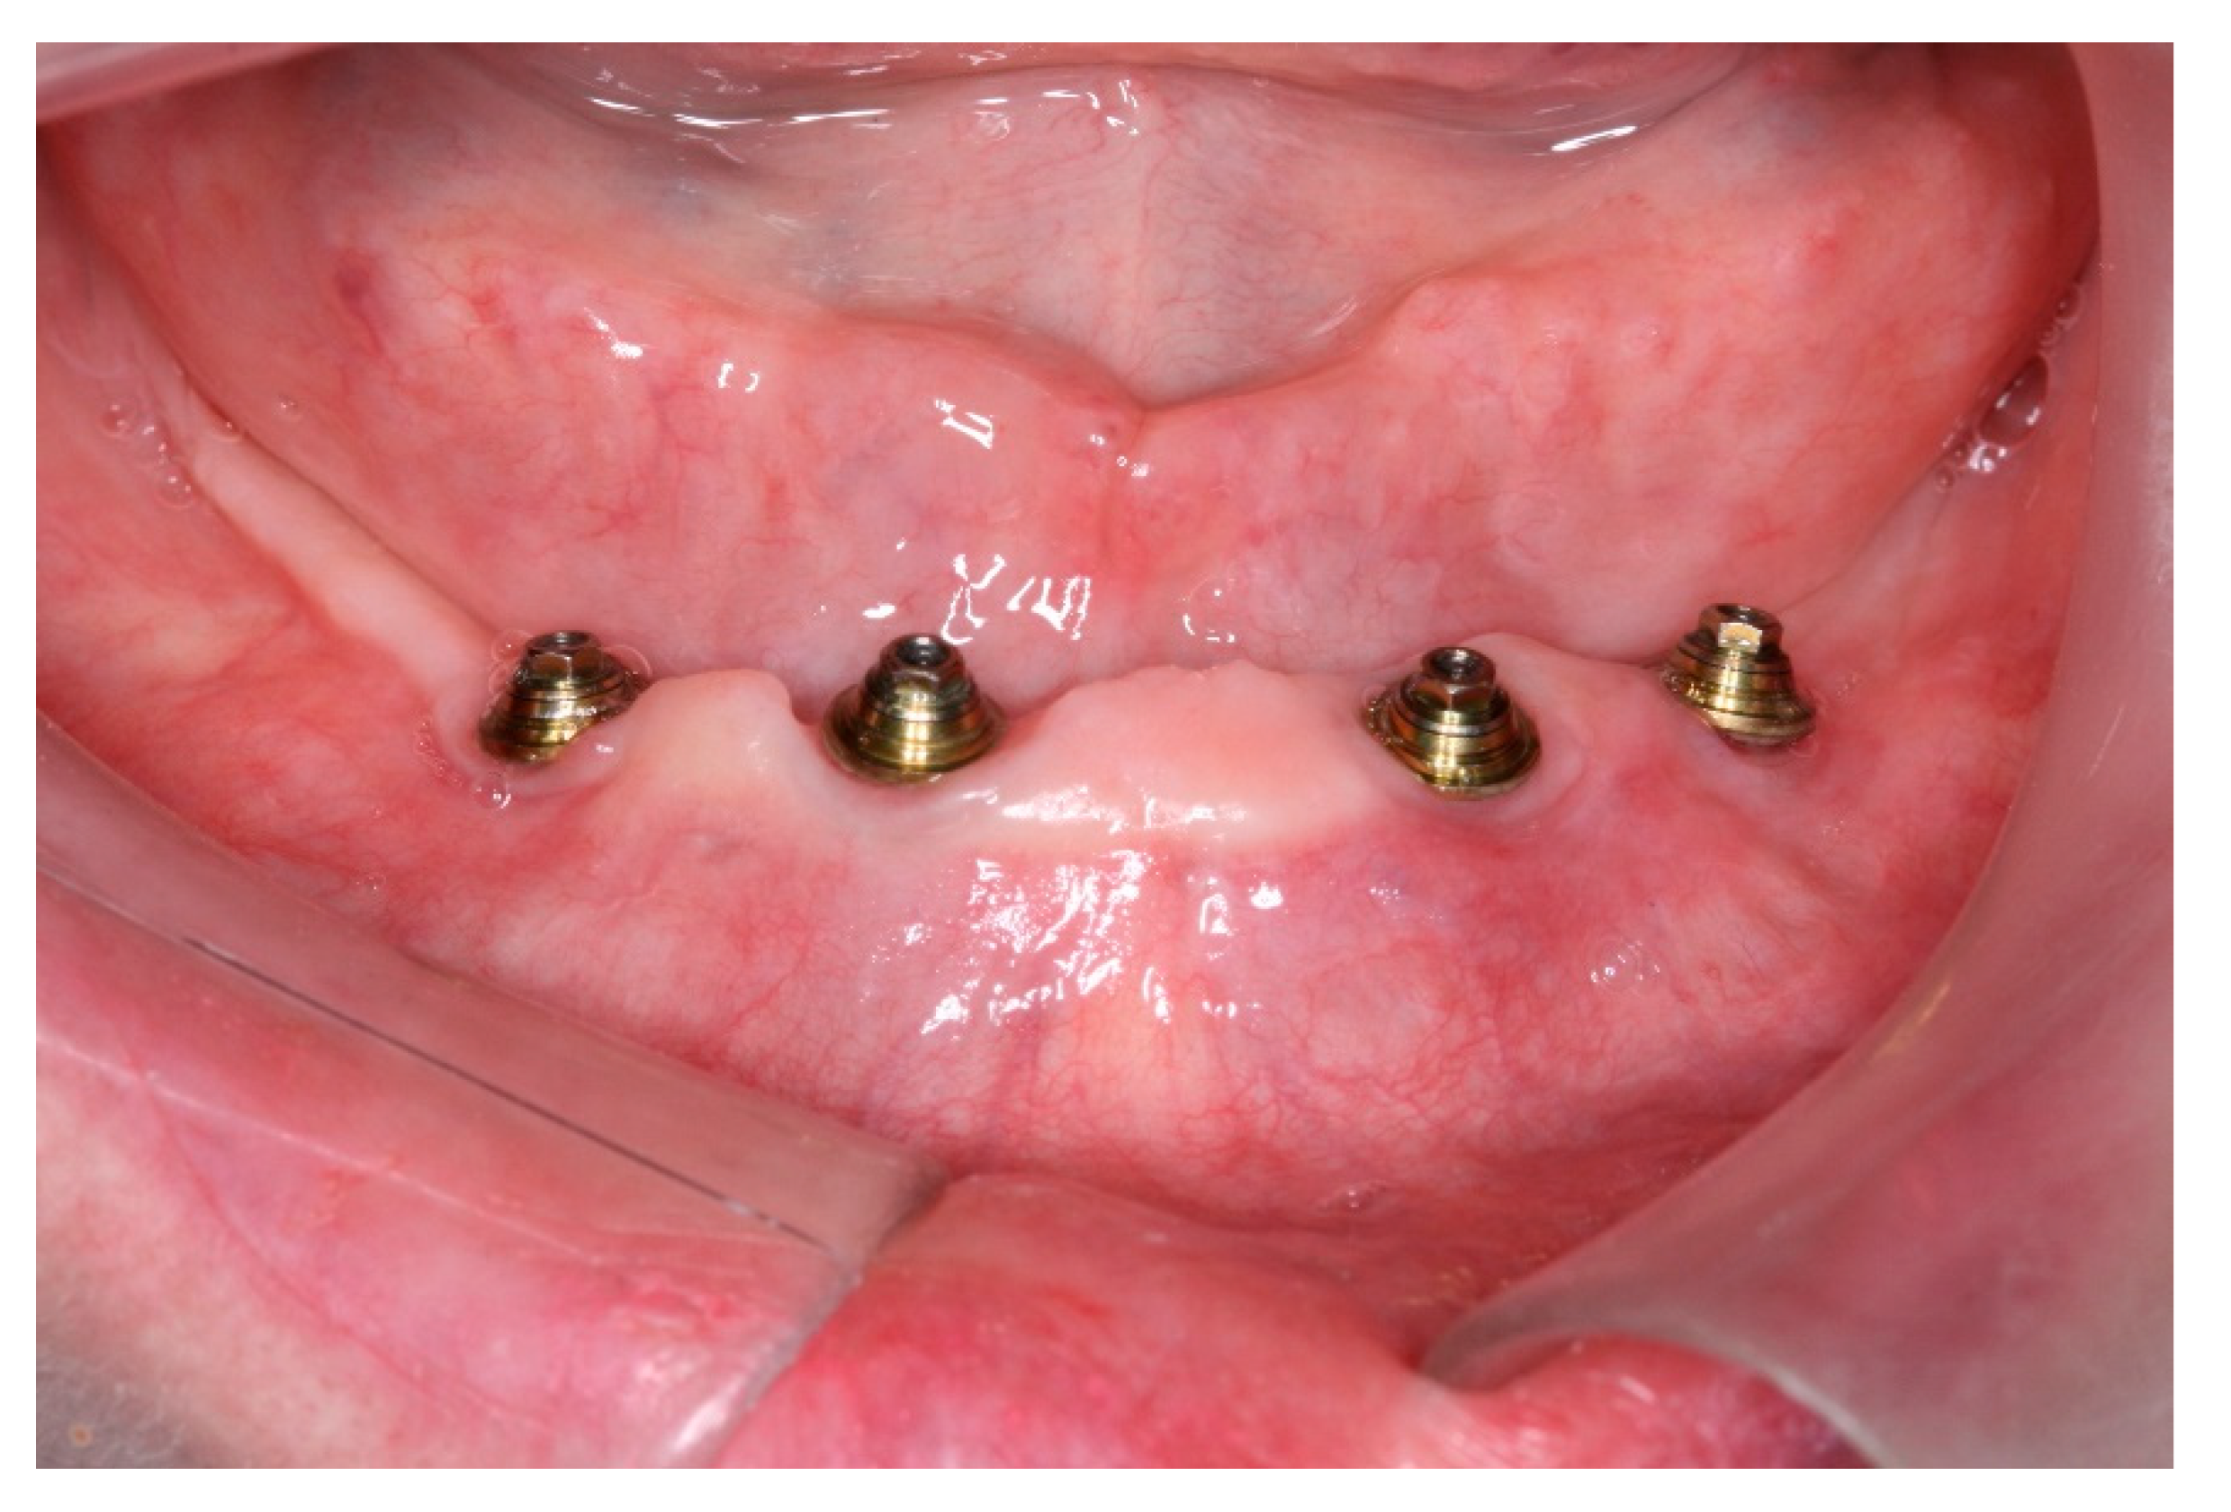

After a healing period of 3 months the patient returned to change que temporary fixed prothesis for a new one, more delicate and with a reinforced metallic bar for a better ferulization of the implants and better dissipation of the stress during function. After removal of the temporary prosthesis we could see the peri-implant mucosa was healthy (Figure 19), without bleeding on probe nor peri-implant sulcus with more than 3mm depth, even around the implants were there were lack of a satisfactory keratinized tissue band, showing us that the patient was being able to maintain the cleansing of the region below the prosthesis. A new fixed rehabilitation over the implants was produced (Figure 20, Figure 21 and Figure 22). 2 years after the surgery we could see on a control panoramic radiograph no signs of bone remodeling above the expected around the implants (Figure 23).

Figure 19. View of the peri-implants mucosa after 3 months of healing.